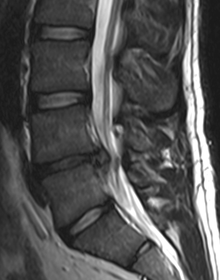

Stage 2: The next stage in degeneration is the loss of disc height causing slackness in the supporting ligaments and resulting inflammation, as seen below. As the discs loose height the supporting ligaments become lax. To make up for this the body will attempt to stabilize the joints by splinting the muscles around the joint. Disc have not blood supply and receive nutrients only through movement. As the muscle splinting progresses the discs slowly starve and loose more height. So the degeneration progresses.

Stage 3: The instability produces abnormal tugging where the ligaments attach at the borders of the vertebral bodies. This changes the electrical potential of the bone from positive to negative allowing positively charged calcium ions to build up a the attachments of the ligaments. The characteristic indication of stage 3 is bone spurs. The disc is dying.

If the disc is traumatically torn or if the degeneration progresses to weaken it the nuclear material can cause bulging of the disc, or can extrude from the disc and hit one of the exciting spinal nerves. This can cause odd sensations (paresthesias), or extreme pain called ‘radicular neuralgia’. If this pain involves the sciatic nerve in the leg it is called sciatica. Usually this occurs in either stage 1, 2 or 3. After this stage of degeneration the disc is usually too dried out and stiff to have extrusions.